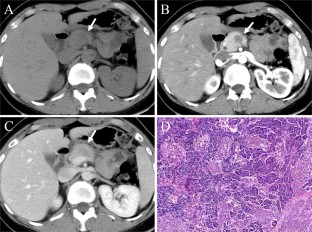

Fig. 3